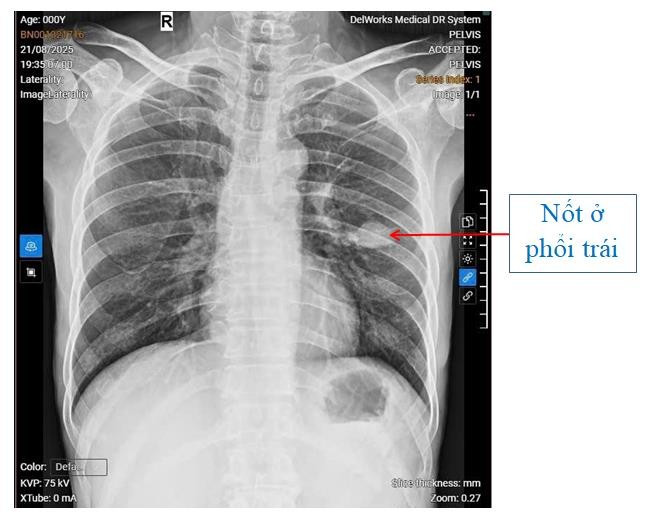

Qua thăm khám và thực hiện các xét nghiệm, kết hợp hình ảnh chụp X-quang phát hiện nốt phổi trái, người bệnh được chẩn đoán: Theo dõi U phổi trái – Viêm dạ dày – Trào ngược dạ dày thực quản độ C.

Hình ảnh phim chụp X-quang của người bệnh T.N.A - Ảnh BVCC